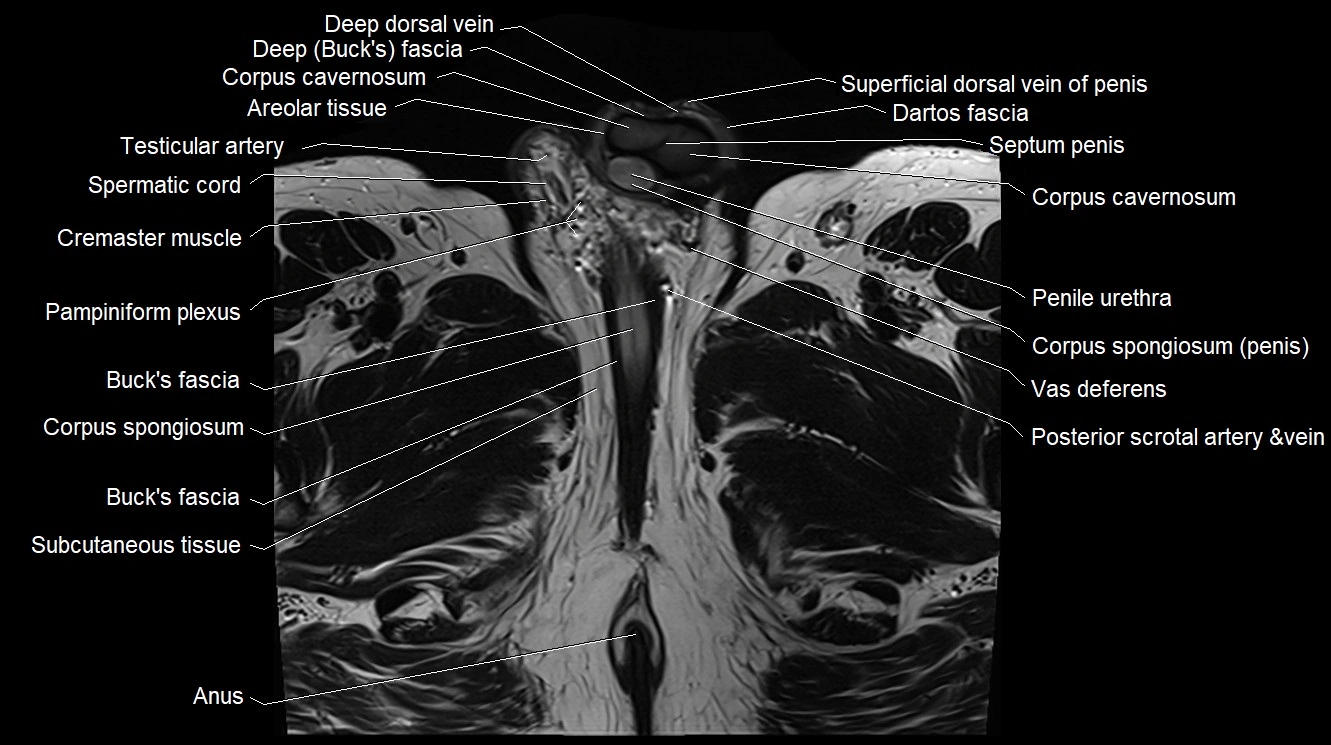

MRI image